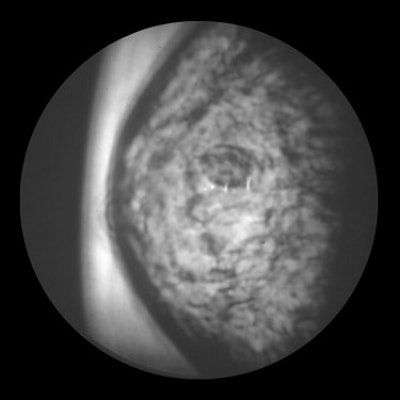

DUS uses a gray scale that correlates white with high sound transmission and dark with low sound transmission, making cysts look relatively white and solid masses look dark.

A fibroademona (above) and a ductal carcinoma (middle) as seen on diffractive ultrasound. Below, normal findings that highlight the different tissue layers in the breast. Images courtesy of Advanced Imaging Technologies.

On DUS, cystic lesions are round, oval, or lobular in shape, with circumscribed margins. Solid masses are oval, lobulated, or irregular in shape, with either circumscribed or ill-defined margins. Malignant tumors exhibit architectural distortion by distorting the pattern produced by the surrounding fibroglandular tissue.

"It’s a promising technique insofar as differentiating cysts and solid masses. If it’s dark on DUS we know it’s solid. But whether it’s benign or not we can’t tell," Hashimoto said.